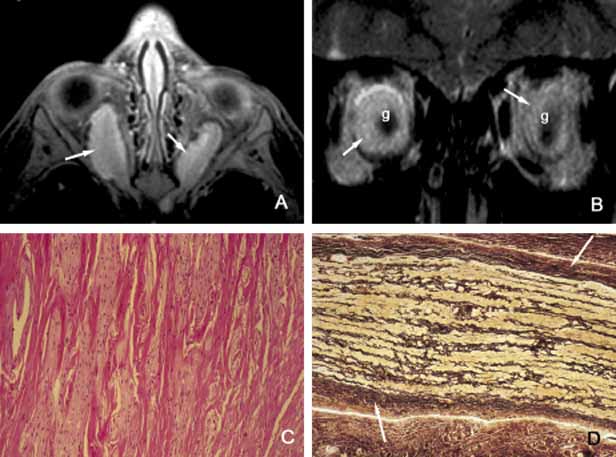

Another type of orbital tumor that originates from blood vessels is hemangiopericytoma, which is a pseudoencapsulated spindle cell tumor composed of vascular pericytes183 (Fig. 17). In these tumors the reticulin network surround the individual tumor cells in hemangiopericytoma as opposed to small groups of epithelial cells in capillary hemangioma. In hemangiopericytoma the tumor cells stain positively with factor VIII, CD34, and occasionally vimentin. The histopathologic pattern that may present considerable pleomorphism with increased number of mitotic figures may vary from one zone to the other. The degree of pleomorphism and high number of mitotic figures are not clear cut indications of malignancy; as a matter of fact, the biological behavior of this tumor cannot be determined based on its histopathologic appearance. Metastatases after many years have been described.184 The best treatment for hemangiopericytoma is surgical excision.

Fig. 17 Hemangiopericytoma. Axial T1-weighted MRI showing a well-encapsulated large mass located in the medial orbit with compression onto the globe and the optic nerve (A). The signal intensity varies within the mass because of its vascular nature. Frame B depicts the well-encapsulated hemangiopericytoma at the time of its removal. Microscopic appearance reveals a mixture of haphazardly arranged spindle-shaped tumor cells with round and oval nuclei and scanty cytoplasms, mixed with a network of sinusoidal spaces and/or abnormally developed blood vessels. Moderate degree of pleomorphism and occasional abnormal mitotic figures are seen in this section (C). Although these malignant histopathology indicators have been reported in tumors that later metastasize; as a rule the biologic behavior of hemangiopericytoma cannot be dependably assessed based on its histopathology. Frame D shows the immunohistochemical staining with vimentin.